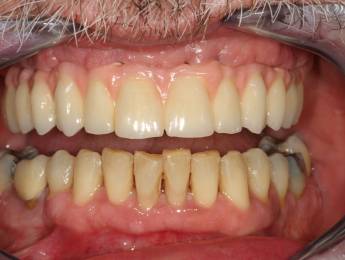

All-on-4 előtte-utána

Az első kezelést követően már egy fixen rögzített hídpótlás készül, amelyet használni tud addig, amíg az implantátumok megfelelően be nem ágyazódnak az állcsontba. Az ideiglenes híd már ebben az átmeneti, gyógyulási periódusban is jelentősen javítja az életminőségét. Ezalatt az időszak alatt is már fog tudni nyugodtan enni, beszélni és mosolyogni is.

Amikor a gyógyulási idő lejár, következik a második szakasz, amely során Ön megkapja állandó, végleges fogait. Ezt követően már úgy fogja magát érezni, mint mielőtt a fogászati problémái elkezdődtek.